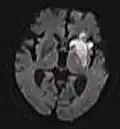

| Diffusion weighted (DWI) | Conventional | DWI | Measure of Brownian motion of water molecules.[17] | High signal within minutes of cerebral infarction (pictured).[18] |

|

Another application of diffusion MRI is diffusion-weighted imaging (DWI). Following an ischemic stroke, DWI is highly sensitive to the changes occurring in the lesion.[44] It is speculated that increases in restriction (barriers) to water diffusion, as a result of cytotoxic edema (cellular swelling), is responsible for the increase in signal on a DWI scan. The DWI enhancement appears within 5–10 minutes of the onset of stroke symptoms (as compared to computed tomography, which often does not detect changes of acute infarct for up to 4–6 hours) and remains for up to two weeks. Coupled with imaging of cerebral perfusion, researchers can highlight regions of "perfusion/diffusion mismatch" that may indicate regions capable of salvage by reperfusion therapy.